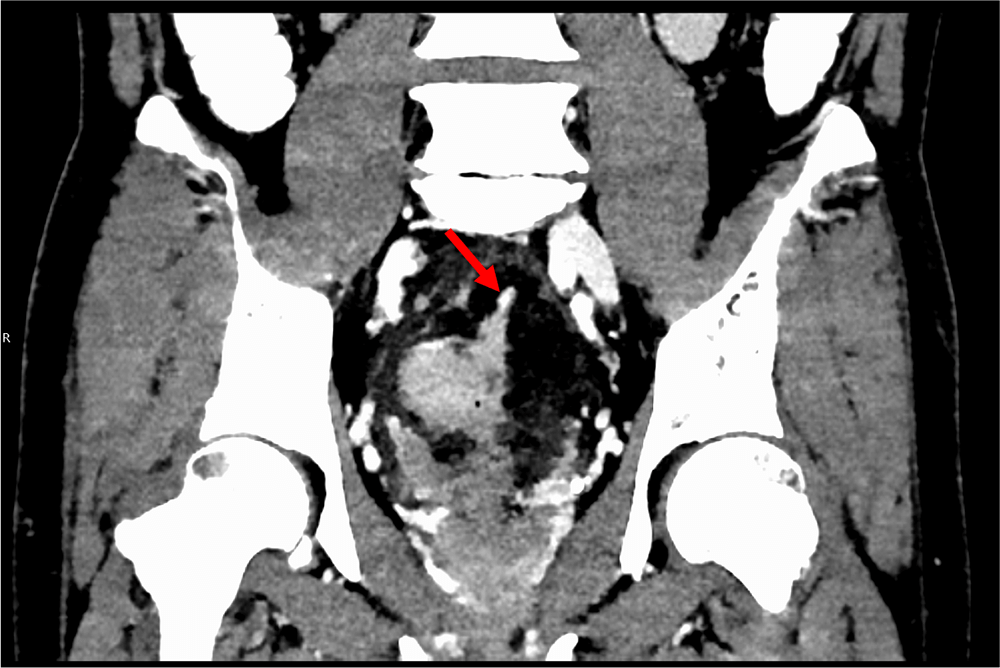

図3.門脈相(120kVp画像)、冠状断

下腸間膜静脈(矢印)に連続するような、EMVIを認める。

図4.門脈相(MonoE 40keV)、冠状断

下腸間膜静脈(矢印)がはっきりと同定でき、EMVIとのコントラストも明瞭になっている。

また直腸癌の予後不良因子である壁外静脈浸潤(EMVI)、tumor deposit(TD) の同定は重要であることが知られている。これらはMRIで診断されることが一般的であるが、造影CT検査でも指摘できることがある。仮想単色X線エネルギー画像(MonoE)は低エネルギー帯でヨードの造影効果が劇的に増加するため、病変や脈管の視認性が向上するので、検出能や診断確信度の向上に寄与すると考えられる。